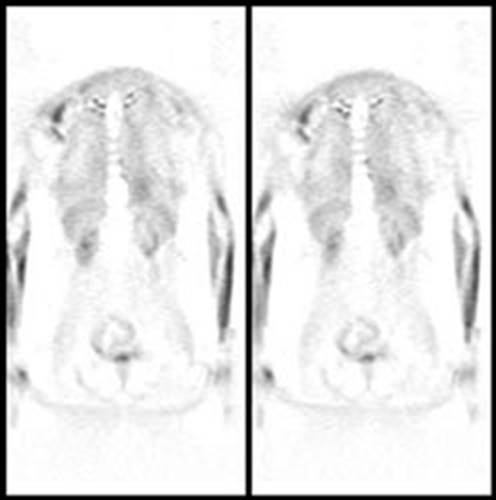

Figure 21 - Marrow activity: The images below are from

two separate patients each showing mild FDG accumulation within the vertebral

bodies.